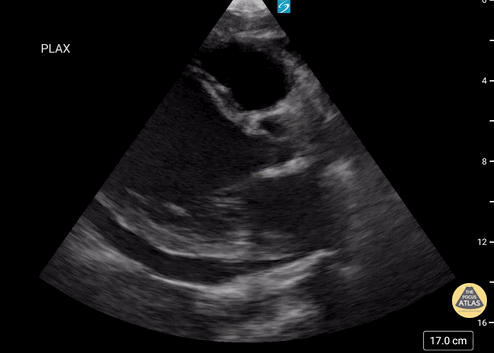

47 year-old male with no cardiac history presenting with shortness of breath and leg swelling for two weeks found to have new onset cardiomyopathy. POCUS echocardiogram showed significant dilation of the LV on parasternal long axis view with reduced EF; EPSS of 23.7 mm. Formal echocardiogram confirmed findings with additional findings including EF <20%, mild dilation of the LA, RA, and RV. While LV is grossly dilated, the significantly increased EPSS correlates with the dramatically reduced EF. Brent Oldham, MD, MPH, PGY-3, Central Michigan University College of Medicine, Emergency Medicine Dan Dunaske, DO, PGY-1, Central Michigan University College of Medicine, Emergency Medicine Brad Buska, MS4, Central Michigan University College of Medicine